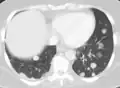

CT image of a lung metastasis

CT image of a lung metastasis -